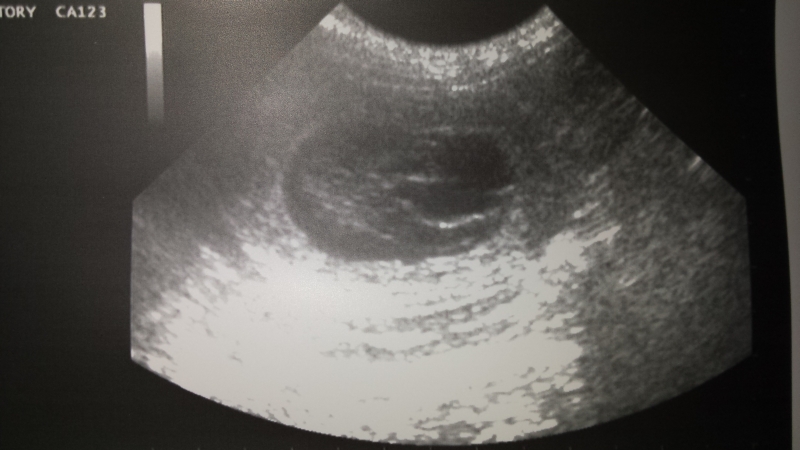

Viel zu früh musste er uns verlassen. Plötzlich und unerwartet riss ihn ein heimtückischer Leberkrebs aus unserer Mitte. Bis zuletzt war Tamy voller Lebensfreude, Energie und Tatendrang, umso schockierender ist sein unerwarteter Tod.